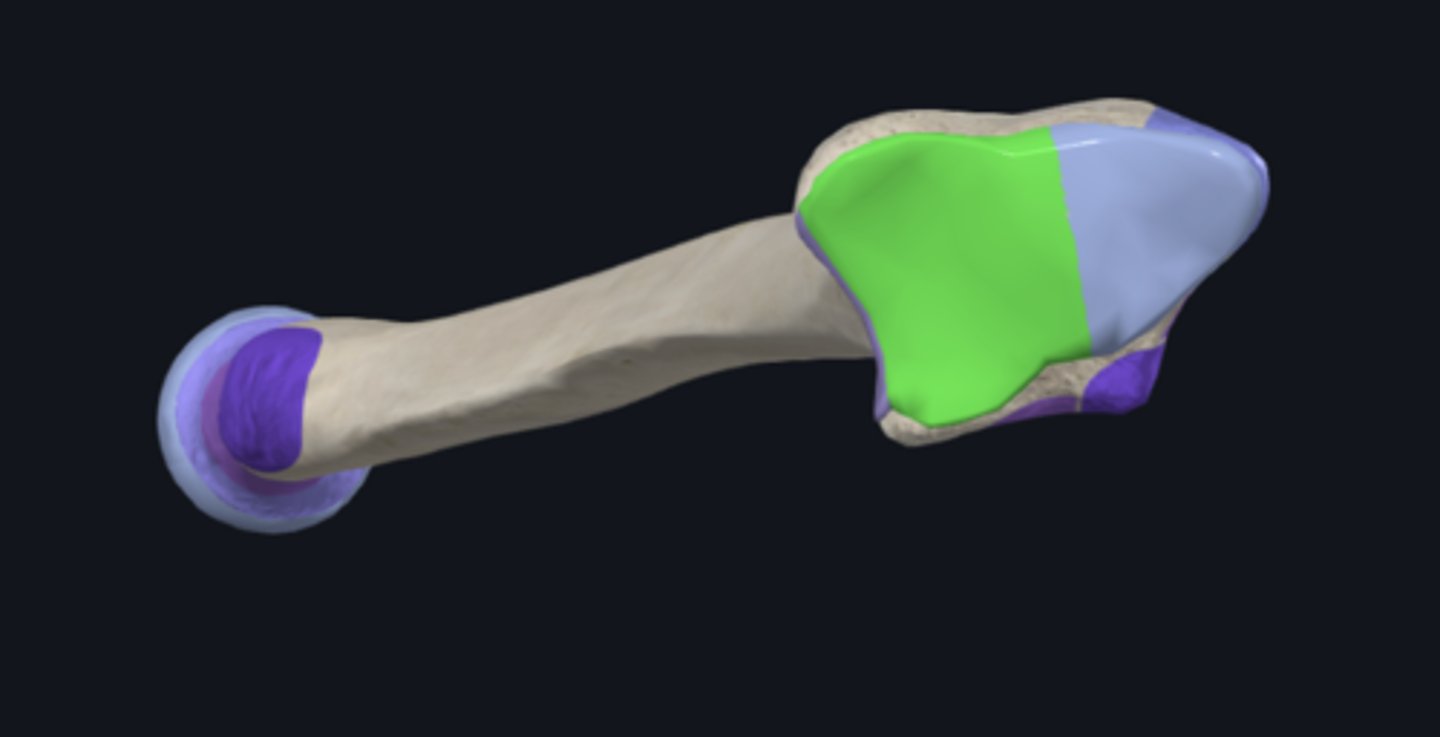

anatomical neck of humerus

body of humerus

condyle of humerus

greater tubercle

head of humerus

lesser tubercle

Capitulum

coronoid fossa

Crest of greater tubercle

crest of lesser tubercle

deltoid tuberosity

groove for ulnar nerve

bicipital groove

olecranon fossa

radial fossa

radial groove

surgical neck of humerus

trochlea